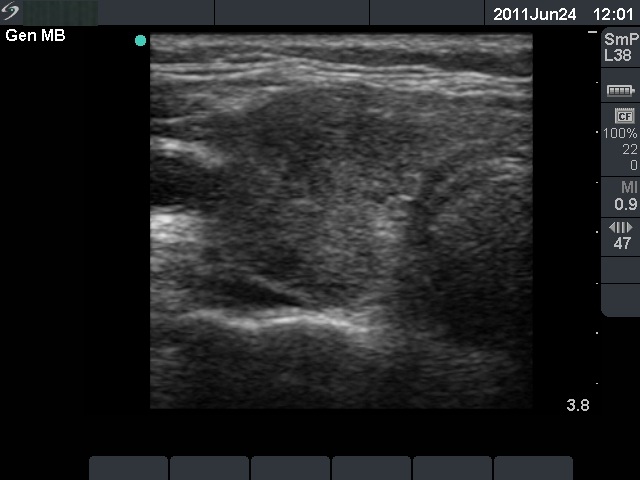

First examination (1st and 2nd rows of images):

Clinical presentation: a 36-year-old woman was referred for the evaluation of a painful thyroid. She had subfebrility. Her complaints began 2 weeks before the examination. 5 years earlier she has been treated for subacute thyroiditis with steroid therapy.

Palpation: both thyroids were painful.

Functional state: subclinical hyperthyroidism (TSH-level undetectable, FT4 18.7 pM/L, FT3 6.96 pM/L, sedimentation rate 33 mm/H, CRP 9.4 mg/L).

Ultrasonography: the basic echo structure of the thyroid was normal with multiple hypoechogenic lesion with ill-defined borders. The vascularization was decreased.